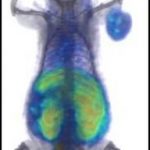

Study: The glow could someday help us use cancer drugs more efficiently — ...

Experimenting with mice, Johns Hopkins researchers report they have successfully used positron emission tomography (PET) scans to calculate in real time how much...